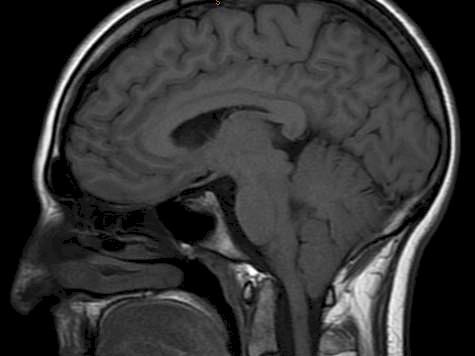

My little sister Alysha has Chiari Malformation and Syringomyelia. In simple terms, her brain is falling out of her head and she needs help!

Alysha is booked in to have surgery in March to try and 'fix her brain'. Although this won't be a cure, it will hopefully help her function better day to day. Unfortunately because it is a rare, chronic condition, it would take her FOREVER to get surgery through the public system. She luckily has health insurance which is covering most of the cost but she has to find an additional $1300 plus any extras that she might need following the Surgery and travel costs back and forth to all of her appointments. We realise that everyone has a lot going on, especially at this time of year. However, if you happen to have a little to give to this cause, it would be so greatly appreciated by Alysha and the family.